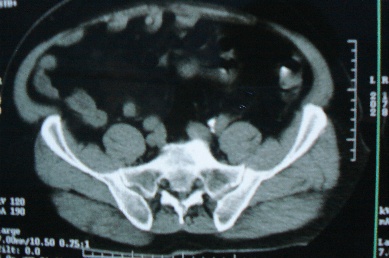

以下是引用zhangzhongshou在2007-6-17 11:53:00的发言:[br]骶管囊肿可能性大,建议mri检查。

以下是引用jinguoji在2007-6-17 14:53:00的发言:[br]骨质未见确切破坏,考虑骶管囊肿可能性大,建议mri检查。